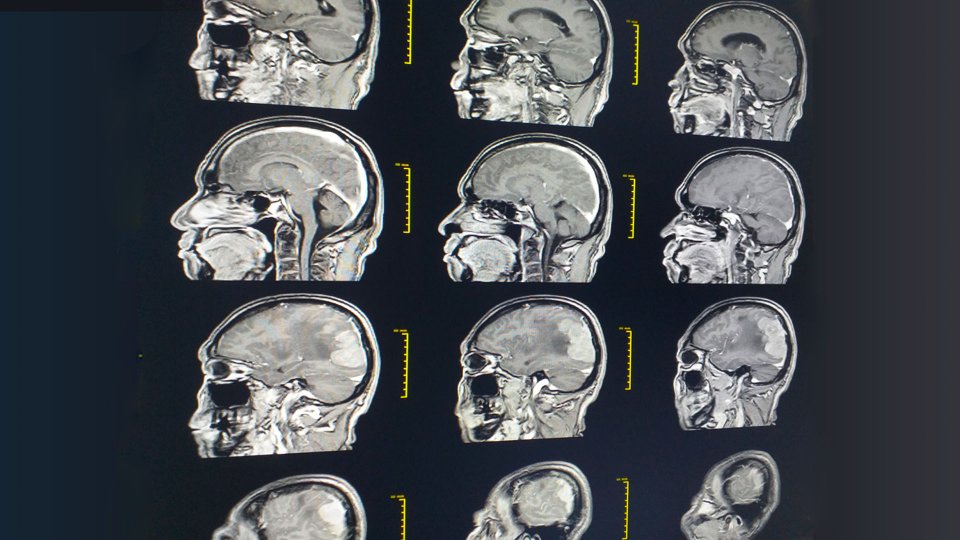

Kafa kaidesi yüz hatlarını oluşturan çeşitli kemik ve kıkırdakların bir araya gelmesiyle şekillenen bir kemik grubudur. Beş ana kemik kafatasının üst bölgesini, göz boşluklarını, burun boşluğunun tavanını, bazı sinüsleri ve iç kulaktaki bazı kemikleri çerçeveler. Bu alan oldukça yoğun ve karmaşıktır, bir dizi açıklığa ev sahipliği yapar ve çok sayıda damar, sinir ve omurilik bu alandan geçer. Beynin altında yer alan kafa kaidesinde veya en üst seviyede bulunan birkaç omur veya omurilikte oluşan benign veya malign kitlelerin çıkarılması için kafa kaidesi cerrahisi kullanılır. Bu bölgenin karmaşıklığı ve erişilmesinin zor olması nedeniyle operasyonlar genellikle minimal invaziv endoskopik tekniklerle gerçekleştirilir. Mikrocerrahi tekniklerin uygulandığı bu tür prosedürler genellikle başarıyla sonuçlanır.

Kraniyotomi: Tümörün endoskopik yöntemlerle ulaşılmasının zor olduğu durumlarda açık cerrahi teknik olan kraniyotomi kullanılır. Kraniyotomi kafatasına yapılan bir kesiden gerçekleştirilen bir prosedürdür. Bazı hallerde operasyon göz kapağından yapılabilir. Özellikle kafa kaidesinin arka tarafındaki yan tümörlerde kraniyotomi tercih edilir. Akustik nevroma gibi tümörlerin çıkarılmasında kraniyotomi yöntemi kullanılır. Meninjiyom, kordom veya kondrosarkom gibi tümörler bazen kafa tabanının arkasında meydana gelir ve bu durumlarda kafa tabanı mikrocerrahisi uygulanamaz. Bu tip tümörlerin çıkarılması için kulakların arka ya da üst bölgesine bir kesi yapılarak operasyon gerçekleştirilir. Göz kapaklarına kraniyotomi işlemi uygulanırken, göz kapağına ince bir kesik atılır. Kafatasından küçük bir parça açılıp buradan kafa tabanının önünde bulunan tümörler temizlenir. Operasyon sonrası yüzde herhangi bir olumsuz etkisi olmaması için plastik cerrahın hazır bulunması gereklidir. Kafa tabanı vücutta oldukça karmaşık bir yapıya sahiptir ve bu yüzden kafa tabanına yapılacak operasyonlar yüksek risk taşır. Beyinde, sinirlerde veya omurilikte oluşabilecek zararlar hastaların kalıcı sağlık sorunları yaşamasına neden olabilir.